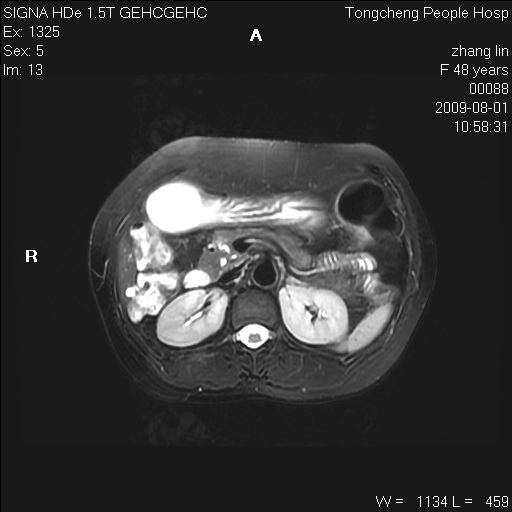

女,48岁。健康体检,彩超发现右肾占位性病变。平素健康。

临床诊断:右肾占位性病变,性质待定(囊肿?肿瘤?)。

上中腹部mr平扫+增强扫描,图像如下:

右肾上极见一类圆形病灶,t1wi呈等信号t2wi呈等高混杂信号,三期增强无强化,边界清---考虑囊肿出血。

同反相位均表现为等信号,病变无强化,考虑含蛋白的囊肿可能,弥散加权相或许有些帮助,